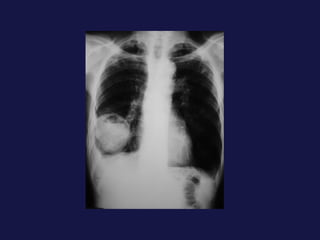

Carcinoma epidermoide ( 30% ). Bronquios centrales, ayuda la citología de esputo. Localización central. Provoca obstrucción bronquial con atelectasia o neumonía postobstructiva sin perdida de volumen mucha cavitación con paredes gruesas e irregulares. 40% lesión periférica,   con bordes espiculados o lobulados. Causa frecuente de pancoast-Tobías.

Tumor central. 60-75% próximos a los hilios. Epidermoides y células pequeñas. Agrandamiento asimétrico del hilio o masa de bordes espiculados. Atelectasia lobular, segmentaria o de todo el pulmón. Sobreinfección del parénquima distal y neumonía postobstructiva, a menudo abscesificada.

Carcinoma epidermoide (30% ). Bronquios centrales, ayuda la citología de esputo. Localización central. Provoca obstrucción bronquial con atelectasia o neumonía postobstructiva sin perdida de volumen mucha cavitación con paredes gruesas e irregulares. 40% lesión periférica, con bordes espiculados o lobulados. Causa frecuente de pancoast-Tobías.

Tumor central. 60-75%próximos a los hilios. Epidermoides y células pequeñas. Agrandamiento asimétrico del hilio o masa de bordes espiculados. Atelectasia lobular, segmentaria o de todo el pulmón. Sobreinfección del parénquima distal y neumonía postobstructiva, a menudo abscesificada.